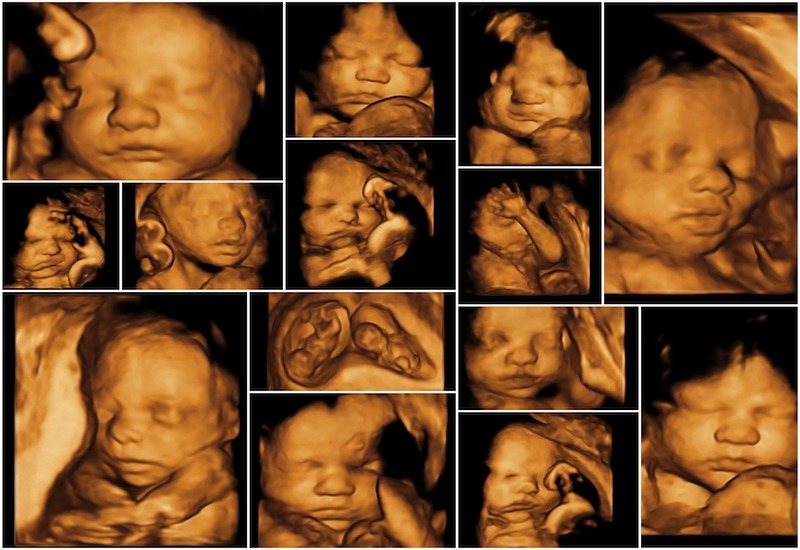

Siêu âm 4D (4 Dimensions) là công nghệ tạo ra hình ảnh 3 chiều kết hợp với thời gian thực (chiều thứ 4 là chuyển động). Nhờ vậy, bố mẹ không chỉ thấy hình ảnh tĩnh mà còn có thể nhìn được những cử động như bé mỉm cười, ngáp, co chân, duỗi tay… Siêu âm 4D thường được thực hiện từ tuần 22 – 28 của thai kỳ, khi thai nhi phát triển rõ ràng nhất về hình thái.

Đặc điểm nổi bật của siêu âm 4D:

• Cho hình ảnh động rõ nét, dễ dàng quan sát khuôn mặt, tay chân, cử chỉ của thai nhi.

• Giúp bác sĩ kiểm tra các cơ quan như tim, não, xương, tứ chi… một cách chính xác.

• Thời gian thực hiện nhanh, an toàn cho mẹ và bé.

• Thường được sử dụng để theo dõi các chỉ số phát triển và kiểm tra dị tật.